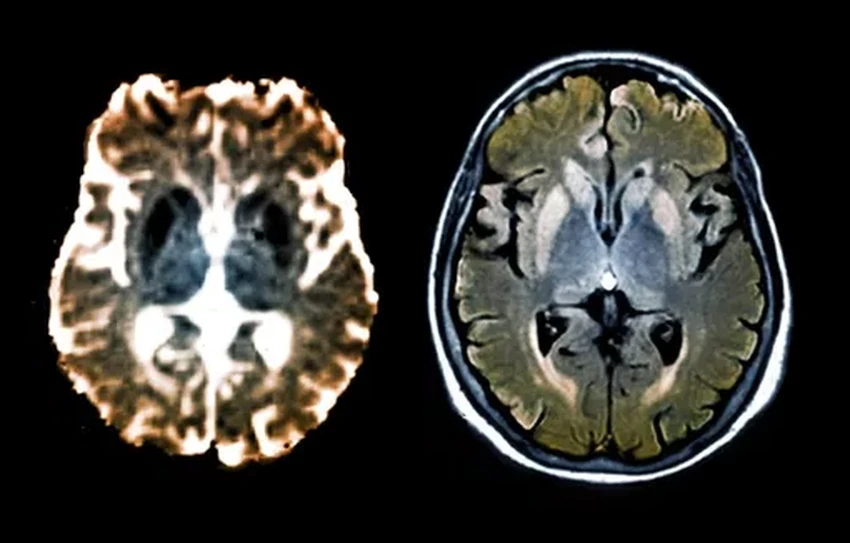

Альцгеймер, Паркинсон, прионные болезни… Объединяет их жуткая поломка на молекулярном уровне: гены начинают штамповать бракованные белки, которые засоряют и уничтожают нейроны. Менять сам геном — дело рискованное. Но природа, оказывается, давно придумала изящный обходной путь — эпигенетическое редактирование. Можно просто «заглушить» проблемный ген, не трогая его код. Ученые взяли на вооружение этот природный механизм и применили «редактор эпигенома» к генам, производящим смертельные прионы. Эксперимент на мышах увенчался успехом: производство ядовитых белков остановилось. Звучит как начало новой эры в неврологии, не правда ли?